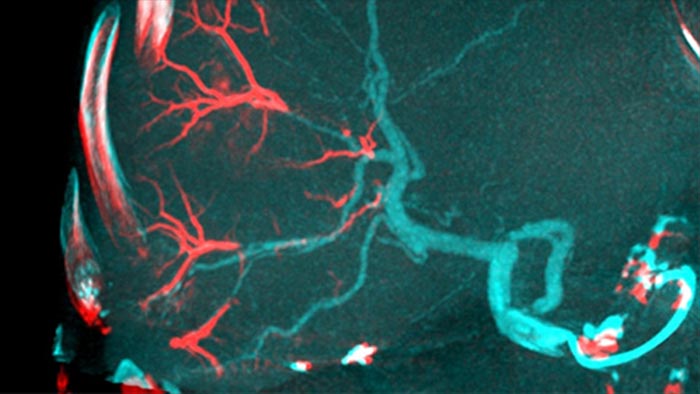

La solución de Detección Automática de vasos Alimentadores puede mejorar significativamente la detección de arterias dependientes. EmboGuide le ayuda a maximizar la eficacia de sus procedimientos TACE, ya que potencialmente mejora su sensibilidad, reduce los falsos positivos y maximiza el acuerdo entre lectores1. EmboGuide también proporciona una guía 3D en vivo eficiente y basada en el flujo de trabajo con detección automática de vasos alimentadores1.

La adopción de técnicas de quimio/radioembolización como TACE y SIRT impulsa la necesidad de estandarización y eficiencia. Caso tras caso, debe localizar de manera confiable y consistente los tumores, identificar todos los vasos dependientes y planificar /ejecutar el enfoque intervencionista apropiado. Nuestra solución de Detección Automática de vasos Alimentadores puede mejorar significativamente la detección de arterias dependientes en comparación con el uso de CT de haz cónico solo. EmboGuide le ayuda a maximizar la eficacia de sus procedimientos TACE, ya que potencialmente mejora su sensibilidad, reduce los falsos positivos y maximiza el acuerdo entre lectores.1

La capacidad de detectar y de distinguir nódulos hepáticos e identificar los recipientes minúsculos del vaso alimentador es crítica para determinar terapia apropiada. Navegar a la región de interés llegando a todos los vasos alimentadores, sin dejar de ser selectivo con la lesión, aumenta la oportunidad de éxito. La confirmación del criterio de valoración del tratamiento y el éxito del mismo mientras el paciente todavía está sobre la mesa aumenta la confianza en los resultados clínicos.